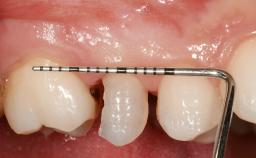

Early Placement of an Implant in a Maxillary Right Central Incisor Site

This 41-year-old female patient was referred to the clinic for the replacement of the right central incisor, since the tooth had developed a root fracture in the long axis that made extraction necessary. The healthy, non-smoking patient was first seen with the tooth still in place. A detailed Esthetic Risk Assessment was performed.The patient was worried about her dental esthetics and had high expectations for a successful treatment outcome from an esthetic point of view. The patient had a medium lip line that displayed parts of the gingiva in the anterior maxilla upon smile.

| Soft Tissue Contour and Volume | Slightly compromised |